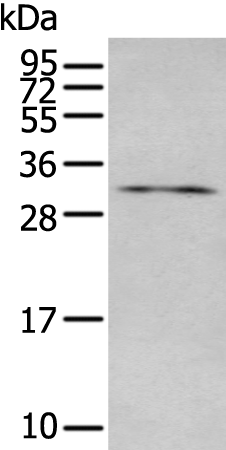

分类: 科研抗体货号: P12757别名: CD129; IL-9R应用: WB,IHC反应种属: Human, Mouse

分类: 科研抗体货号: P12776别名: LAT1; pp36应用: WB,IHC反应种属: Human, Rat